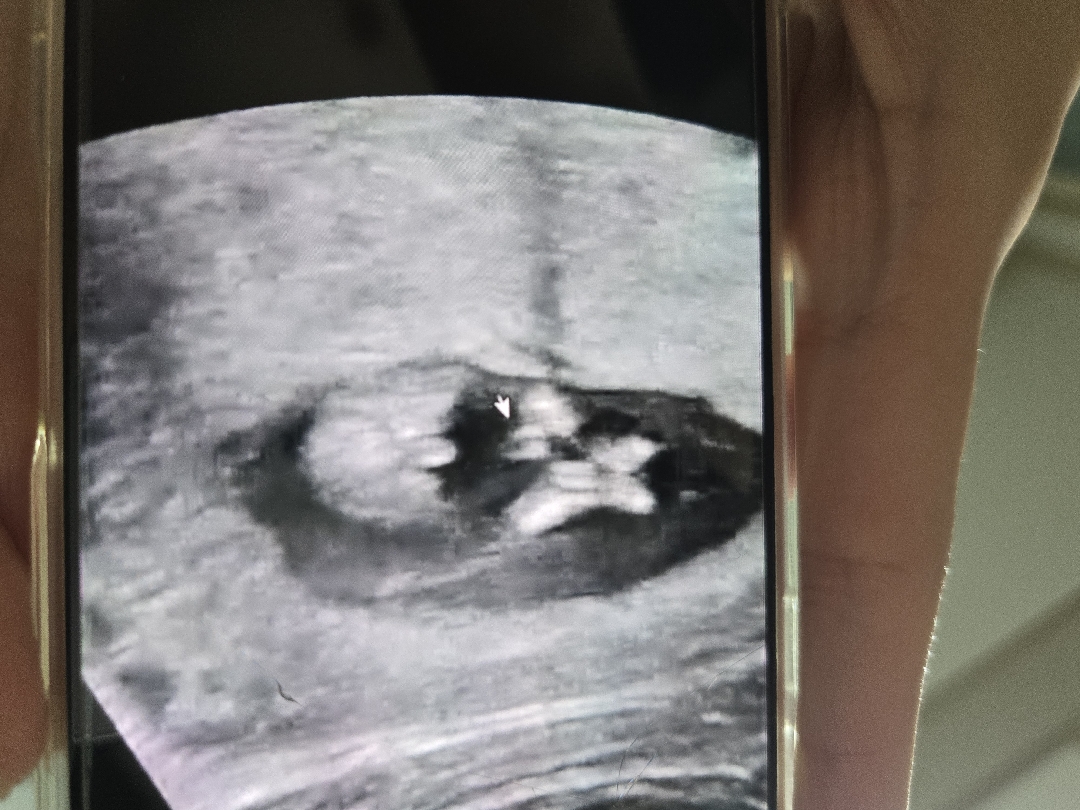

12주 성별 예측 가능할까요??

12주차 밑에서 찍은 사진입니다!🥰 ㅠㅠ궁금해서 잠이 안오네요😭

크기가 확크게 잘보이면 거의 아들이라고 하더라구요😂12주4일인데 잘보여서 저도 아들로 생각하고있답니다!

아둘에 한표요 저는 딸인데 12주 촘파에 저 각도 사진 다리사이 깨끗해요 이고 말구 옆에서 찍은 각도를 봐야해요~~

이 시기엔 둘 다 비슷하게 생겨서 구분하기 힘들대요~ 정확한 건 16는 되어야 알 수 있지 않을까 싶어요ㅠㅠ